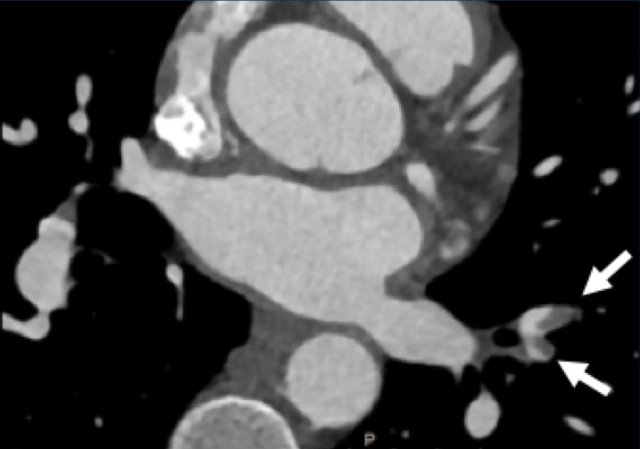

Napkin-ring sign

The Napkin-ring sign is a qualitative high-risk plaque feature

on CTA (13).

It is defined as a central low-attenuation area adjacent to the coronary lumen

and a higher “ring-like” attenuation tissue surrounding this central area (14).

On histology, the area of low-attenuation corresponds to the necrotic core,

while the “ring-like” outer area correlates with fibrous plaque tissue.

The Napkin-ring sign is strongly associated with major adverse

cardiovascular events (15).